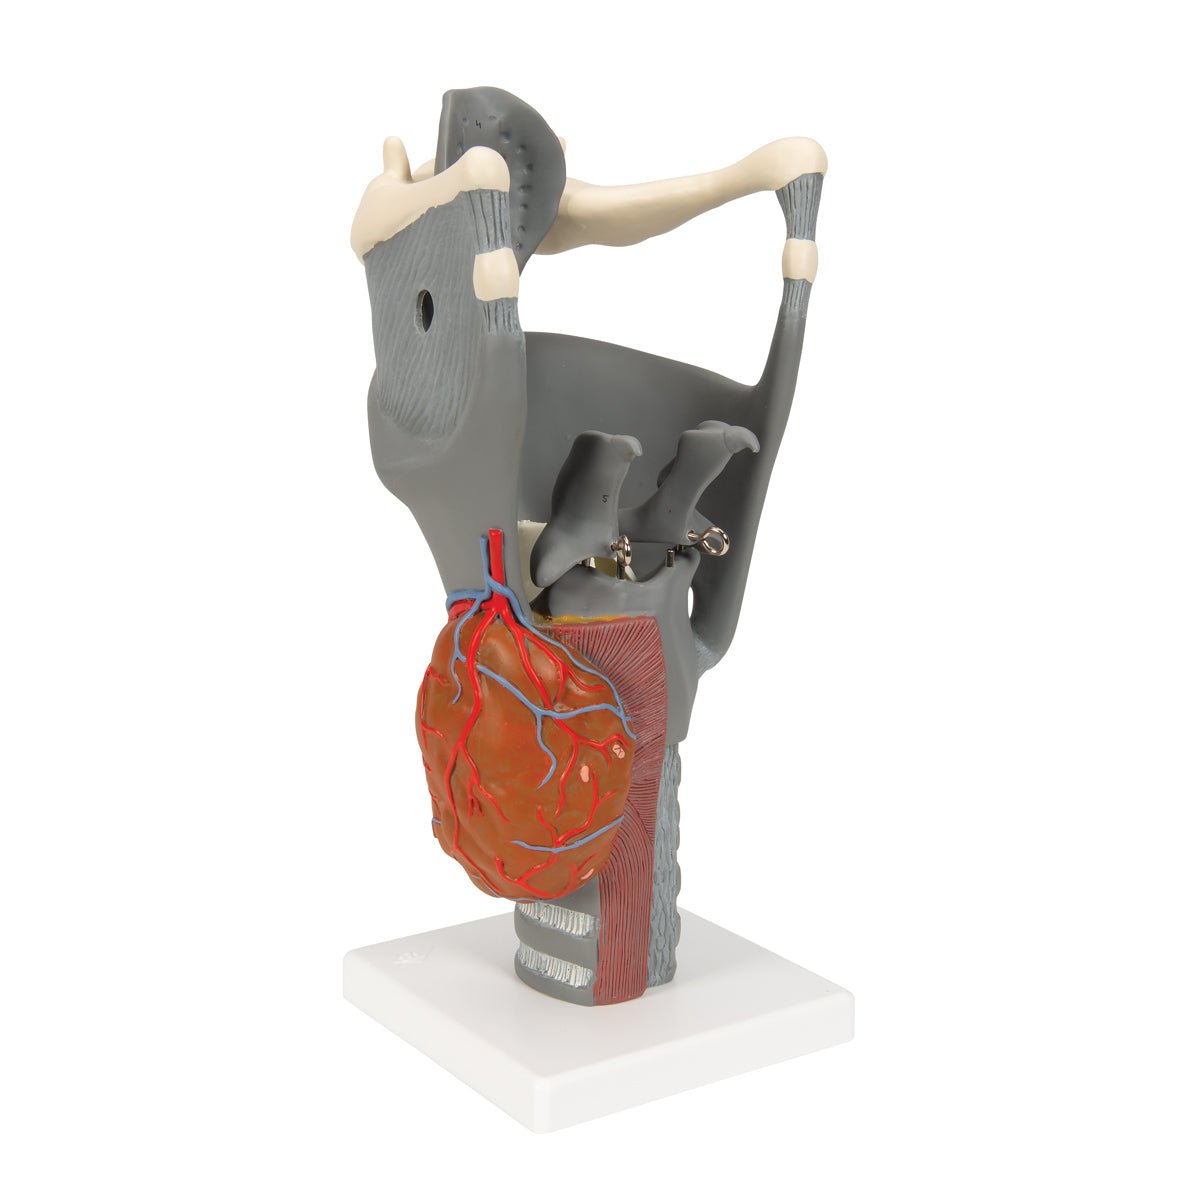

Salg af anatomiske modeller er det bærende element i eAnatomi, selvom vi også bruger mange ressourcer på at udvikle vores egne anatomiske materialer som fx plakater. Anatomiske modeller anvendes til forskellige formål og kan både vise afgrænset væv, organer samt organsystemer. Søger du en simpel model af knoglevæv eller måske en avanceret torso-model baseret på MRI teknologi, kan du finde det hele på eanatomi.com.